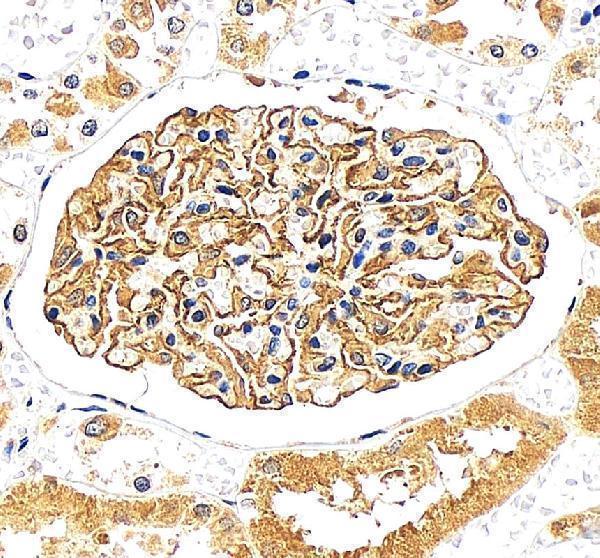

Almost exclusively expressed in the podocytes of fetal and mature kidney glomeruli.